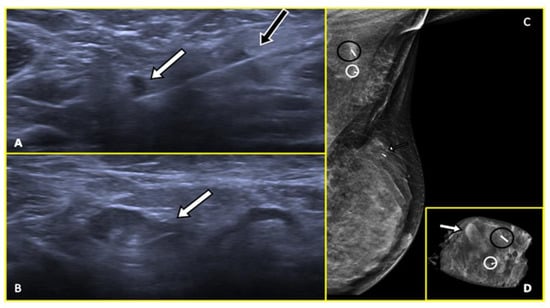

2.1. Marker Clips and Intraoperative Ultrasonography